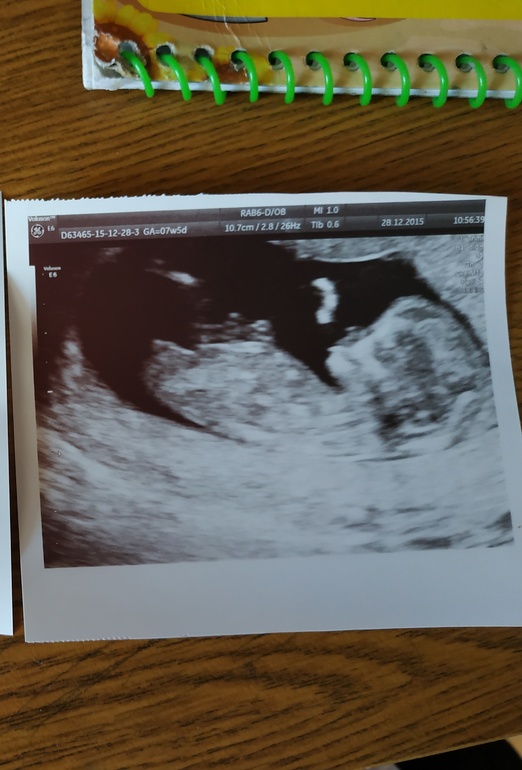

Похоже совпадает с нашими результатами. Это вчерашнее УЗИ (предположительно мальчик)